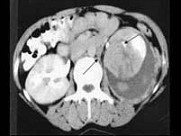

- 多项选择题女,26岁, 临床诊断为绒毛膜癌,行经腹子宫全切术后1月, CT检查如图所示,下列说法正确的是 ( )

A、左肾周可见低密度区,增强后无强化,其内有散在的片状稍高密度影

D、考虑为绒毛膜癌肾转移

E、合并有左肾周自发性血肿